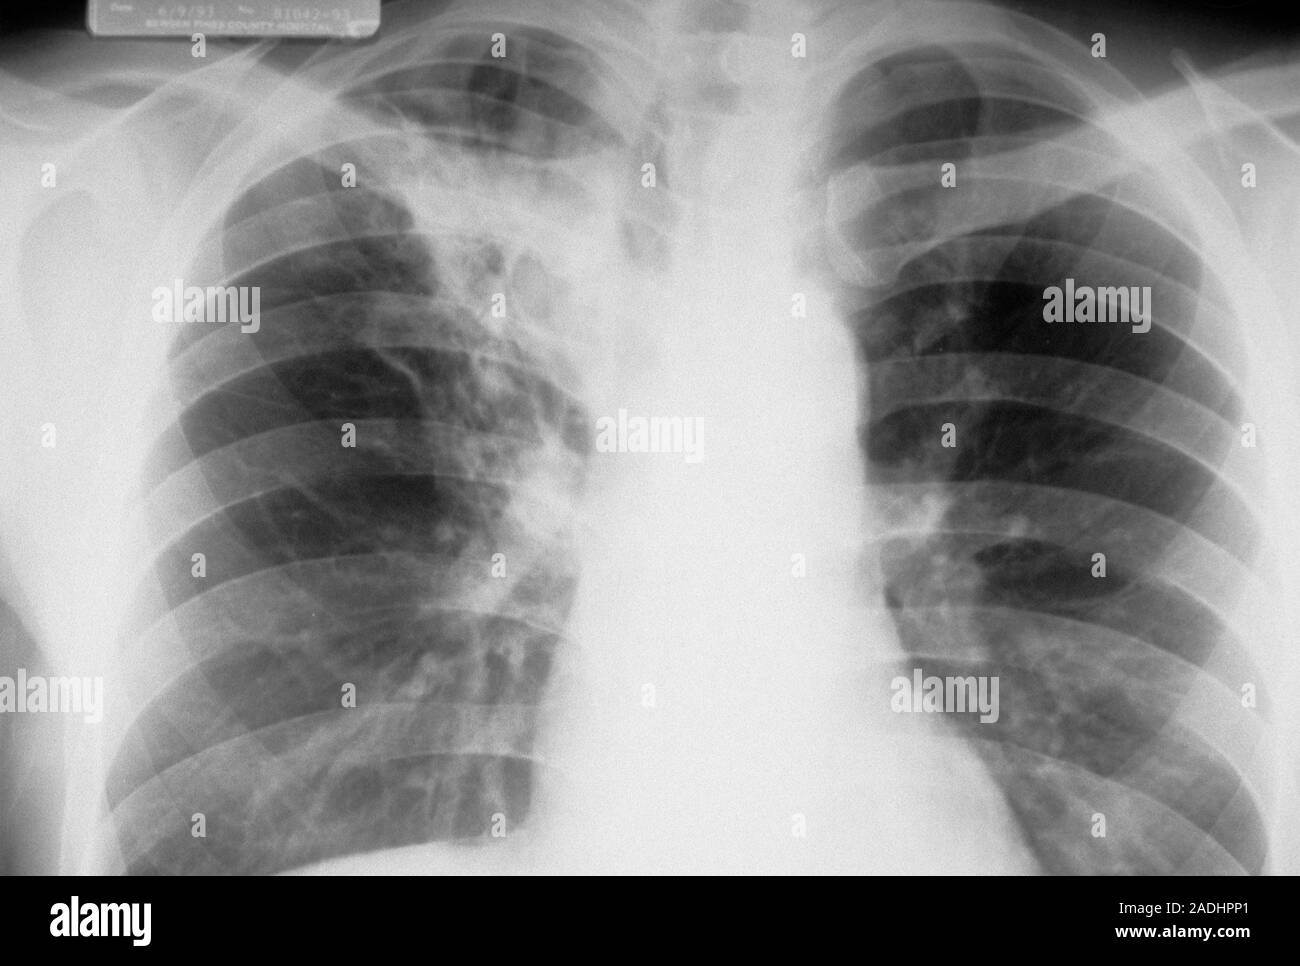

Ein Fleck auf der Lunge, im medizinischen Kontext oft als Lungenrundherd oder Lungenknoten bezeichnet, ist eine umschriebene, meist rundliche Verschattung, die auf einer Röntgenaufnahme des Brustkorbs oder einer Computertomographie (CT) der Lunge sichtbar wird.

Zuerst wird die Größe, Form und Dichte des Flecks genau beurteilt. Eine CT-Untersuchung mit Kontrastmittel kann hier oft detailliertere Informationen liefern als eine einfache Röntgenaufnahme. Beispielsweise kann ein "verkalkter" Fleck eher auf eine alte, ausgeheilte Entzündung hindeuten.

Beispiel: Ein kleiner, glattrandiger Fleck von 5 mm Größe, der in einer Voruntersuchung vor zwei Jahren bereits vorhanden war und sich nicht verändert hat, wird in der Regel als unbedenklich eingestuft.